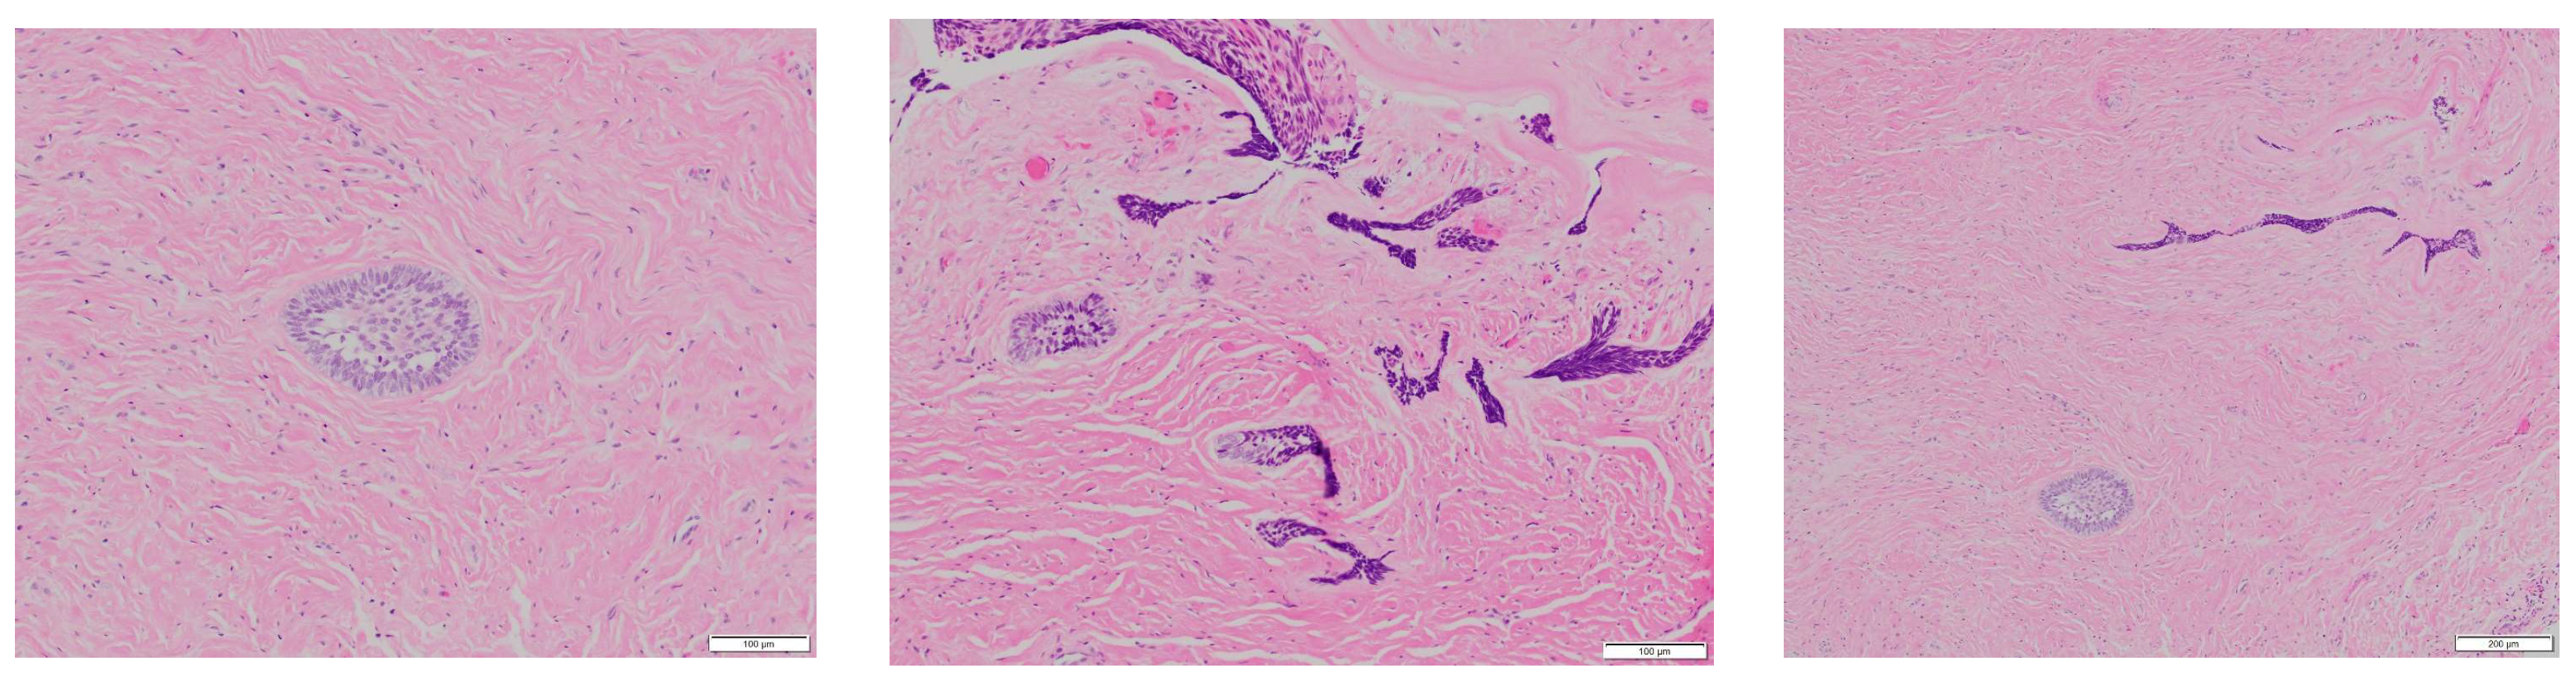

The specimen showed evidence of cyst epithelial lining that underwent ameloblastic differentiation and scattered islands of neoplastic epithelial cells in the adjacent connective tissue, thus proving mural involvement (Figure 6 and Figure 7).

Figure 6. H&E (low and medium power views, (100 μm, 500 μm, 100 μm), from left to right): The cyst epithelial lining shows ameloblastic differentiation with hyperchromatic basal epithelial cells exhibiting reverse polarization. Neoplastic epithelial islands exhibiting ameloblastic differentiation are noted in the connective tissue consistent with mural involvement.

Figure 7. H&E (medium and high power views, (100 μm, 100 μm, 200 μm), from left to right): Scattered epithelial islands exhibiting ameloblastic differentiation are noted in the connective tissue wall of the cyst consistent with mural involvement. The peripheral cuboidal or columnar cells in the epithelial island appear hyperchromatic and exhibit reverse polarization. The central cells are loosely arranged mimicking the stellate reticulum.